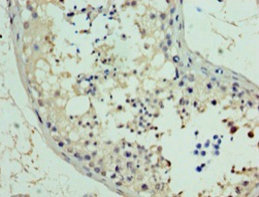

Immunohistochemistry of paraffin-embedded human testis tissue using PA889102LA01HU at dilution of 1:100